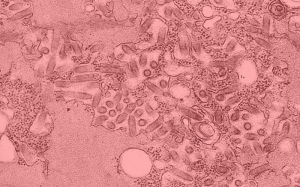

拉沙熱病毒是沙粒病毒科沙粒病毒屬成員。病毒顆粒從圓形到多形,有囊膜,病毒包膜表面有“T”型突起,長度7-10nm,由病毒糖蛋白組成。病毒基因組RNA以環狀核衣殼的形式存在於病毒粒子中,長度在400nm-1300nm之間。病毒粒子內部通常含有電子緻密顆粒,在電鏡下呈沙粒狀紅色,沙粒病毒就是因此而得名的,其電子緻密顆粒是宿主的核糖體組分。